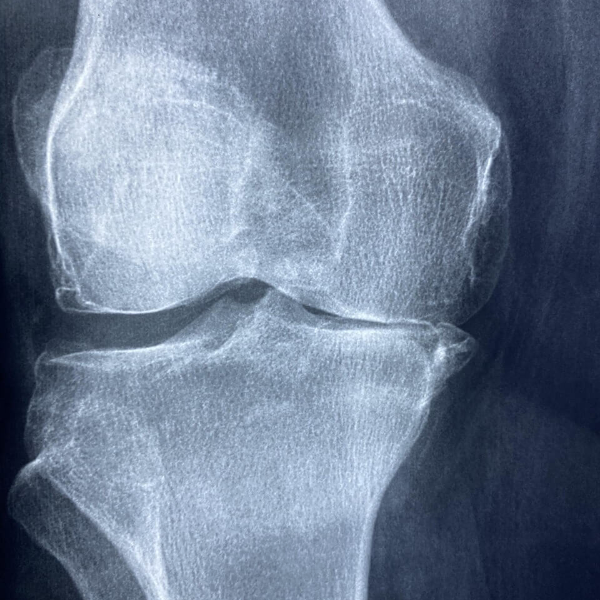

관절이 뻣뻣하고 삐걱거리는 느낌이 드나요? 콘드로이친은 연골의 수분 보유와 탄력을 지켜주는 대표 성분으로 잘 알려져 있습니다. 최근에는 철갑상어(스터전) 유래 콘드로이친처럼 원료 차별화를 내세운 프리미엄 원료가 주목받고 있는데요. 이 글에서는 철갑상어 콘드로이친의 정의부터 효능, 복용법, 주의사항, 제품 선택 팁까지 한눈에 정리했습니다.

콘드로이친은 연골의 수분을 붙잡아 두는 역할을 하여 관절의 마찰을 줄이고 움직임을 부드럽게 만듭니다. 덕분에 관절의 뻣뻣함이나 걸을 때 느끼는 불편감을 줄이는 데 도움을 줄 수 있습니다. 특히 중년 이후나 관절 사용이 많은 분들에게 보조적인 관리 수단이 됩니다.

철갑상어 콘드로이친은 연골 세포와 기질(매트릭스)의 손상을 늦추는 보조 작용을 기대할 수 있습니다. 단독으로 쓰이기도 하지만, 보통은 글루코사민, MSM, 히알루론산과 함께 배합된 제품이 많아 복합적으로 연골 보호 시너지를 추구합니다.

걷기, 계단 오르기, 가사노동 같은 일상 활동에서 관절의 부담을 줄여 움직임의 편안함을 돕습니다. 관절이 덜 뻣뻣하면 자연스럽게 활동량이 늘어나고, 이는 전반적인 생활의 질과도 연결됩니다.